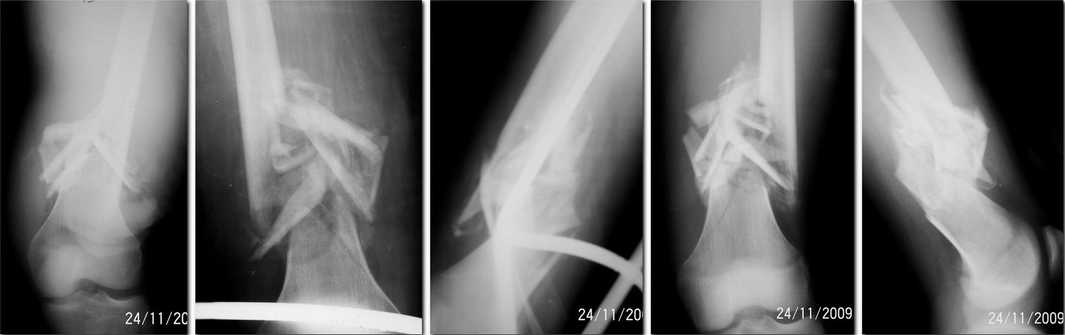

Сегодня кинули аппарат. Мнение уважаемых коллег повлияло на тактику лечения) Всем спасибо. Мозоль поломали, длина есть, осевые деформации небольшие. Выложу снимки после окончательной коррекции думаю дней через 10.

На операции не сложилось впечатление о невыполнимости одномоментной коррекции и штифтования.

В коленном суставе контрактура до 140гр.

По поводу импланта - аппарат собирался из старых запасов, очень старых...